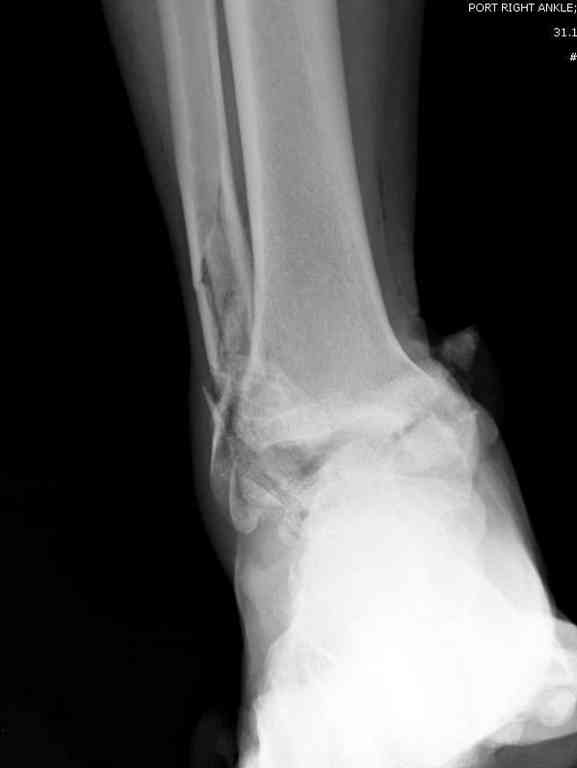

Прошу коллег помочь советом.3 дня назад поступила пациентка 23 года с переломом шейки ладьевидной справа, переломом лодыжек и заднего края б/берцовой кости со смещением и подвывихом кзади, переломом внутреннего мыщелка правого бедра без смещения. Дежурными хирургами проведена репозиция в левом г/ст суставе успешная, попытка репозиции таранной кости ухудшило положение отломков. Планируем провести повторную репозицию и фиксацию винтами. 1. Закрытая репозиция рентгенконтоль интраоперационный (аппарат Арман) ификсация из заднее-наружного доступа. 2. При неудачной закрытой репозиции переходим на открытое вправление двумя доступами медиальным и латеральным "по ходу оси таранной кости" и через дополнительный задний доступ вводим винты кортикальные 4,5 мм или 3,5 мм 3. после открытой репозиции фиксация двумя винтами через боковые доступы погружая их под суставную поверхность Сергей Зырянов ЦРБ Новосибирская область

Здесь на фото примеры:

Переломовывих тарана с повреждением медиальной стороны. Через 4 часа после поступления проведена репозиция и фиксация тарана после Irrigation&Debridment. Частичное несращение медиальной лодыжки не беспокоит, вернулся к активному образу жизни. Полная нагрузка разрешена через 11 недель. Финальные снимки через 11 месяцев.

Второй случай прооперирован вчера.

10 дней назад поступил с открытым повреждением медиальной лодыжки и переломо вывихом таранной кости. Ургентно сделана репозиция с наложением наружного фиксатора + Irrigation&Debridment.

Во время репозиции выявили повреждение заднего сухожилия м. тибиалис и задней большеберцовой артерии. Медиальную рану удалось закрыть частично и установлен вакуум.

Дважды провели Irrigation&Debridment с заменой вакуума.

Вчера провели фиксацию.

Из-за многооскольчатости дистальной части малоберцовой, где невозможно было провести фиксацию шурупами, перелом зафиксирован подпирающей пластиной, которая должна служить дополнением отсутствующей дистальной части малоберцовой (lateral cortex substitute).

Для стабильности два шурупа на синдесмоз.

Медиальную рану с приближенными краями продолжаем вакуумировать (KCI). Наружный фиксатор оставлен на пару недель, надеюсь, небольшая рана будет гранулировать и закроется без кожной пластики. Фиксация медиальной ложыжки не планируется.